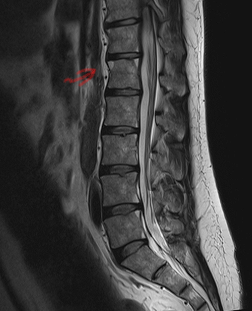

Achado da seta?

Sinal de Romanus.

Edema da medular, de canto, junto à entese. Cronicamente tem-se lipossubstituição/irregularidade.

Paciente com diagnóstico de Spa. Qual achado da seta?

Espondilodiscite de Anderson.